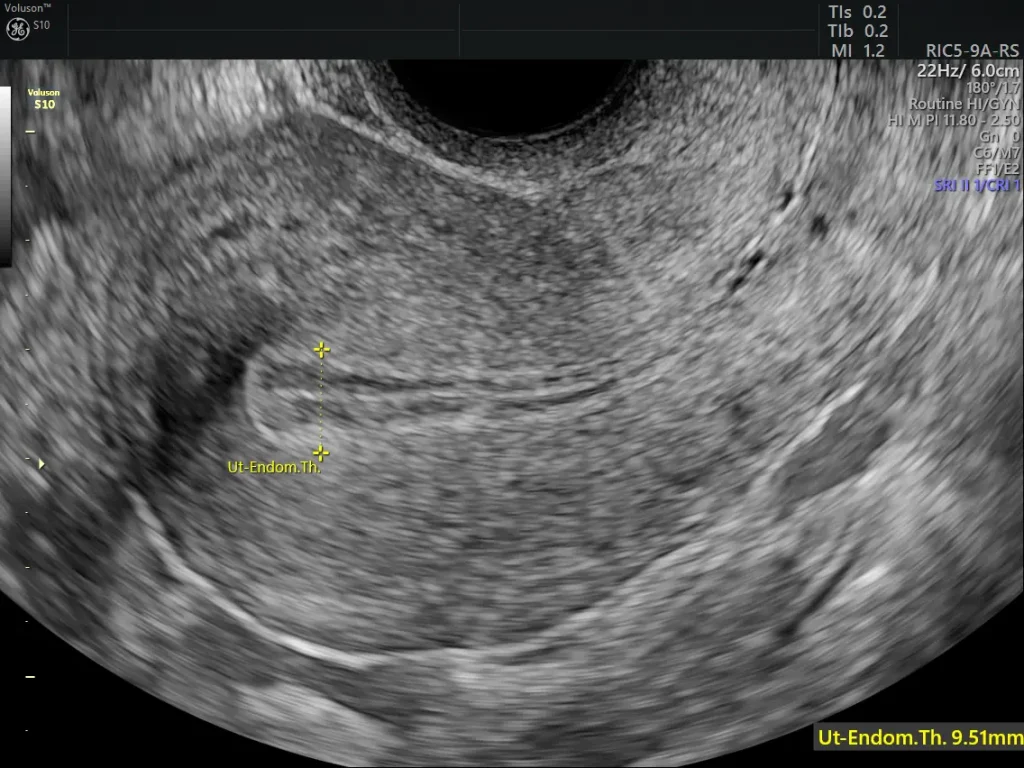

Endometrial Hyperplasia: Symptoms, Causes, Diagnosis, and Treatment

Endometrial Hyperplasia: Symptoms, Causes, Diagnosis, and Treatment Home / Changes in menstrual patterns are often the first sign that something within the reproductive system may need attention. While many irregularities are linked to temporary hormonal fluctuations, some may indicate underlying conditions that require medical evaluation. One such condition is endometrial hyperplasia, a disorder involving abnormal […]